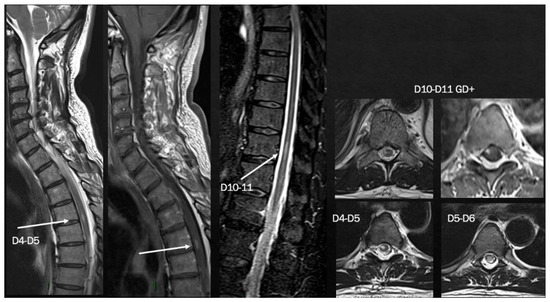

2. MS Onset after SARS-CoV-2 Exposure

| Case 4 | 4 weeks | SC | SC | + | + | + | +/+ |

| Fragoso et al. [58] | 6 months | SC | ST, SC | + | + | - | +/+ |

| Avila et al. [59] * | 2–6 weeks | 40% SC 40% ON 20% BS | NA | NA | + | 80% - 20% + | NA/+ |

| Feizi et al. [60] | 1 week | SC | SC | + | + | NA | +/+ |